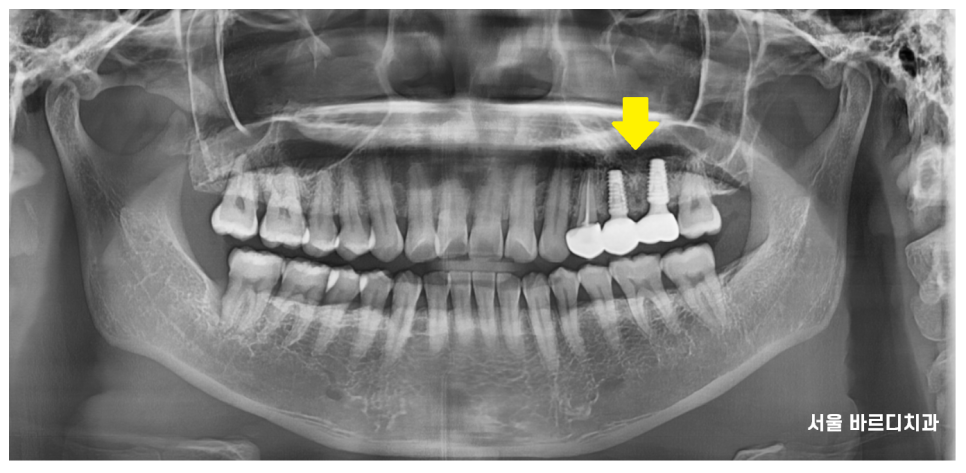

23.11.13

사진은 완성 후 3개월 뒤 정기검진 오셨을 때

사진인데요~~

4월달에 덕풍동 임플란트 식립하고

9월에 완성해드렸어요.

위에 어금니 평균적인 완성 기간인

5개월 정도 걸렸네요~~!